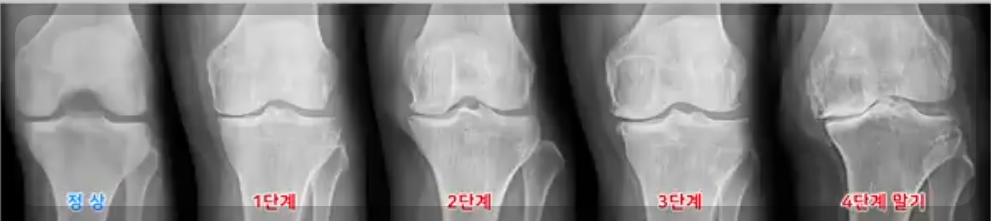

인공관절은 무릎에 통증과 뼈와 뼈가 맞닿아 무릎통증과 마모절감 수술에 제공되는 의료기기입

니다. 무릎통증이 너무 심해 걷지 못하게 되어 인공관절 수술을 하게 되는 것입니다. 매우 심각한 무

릎통증과 걷지도 못하게 되는 퇴행성 관절염 4기가 되기 전 진단을 받고 치료하는데 관심을 가져야

한다.

① 무릎인공관절 수술은 X-ray상으로 퇴행성 4기, 지속적인 통증, 비수수적 치료를 박아도 호전이 없을 때 해야 한다.

퇴행성관절염 4기는 연골이 거의 다 마모가 된 뼈와 뼈가 맞닿은 상태입니다.